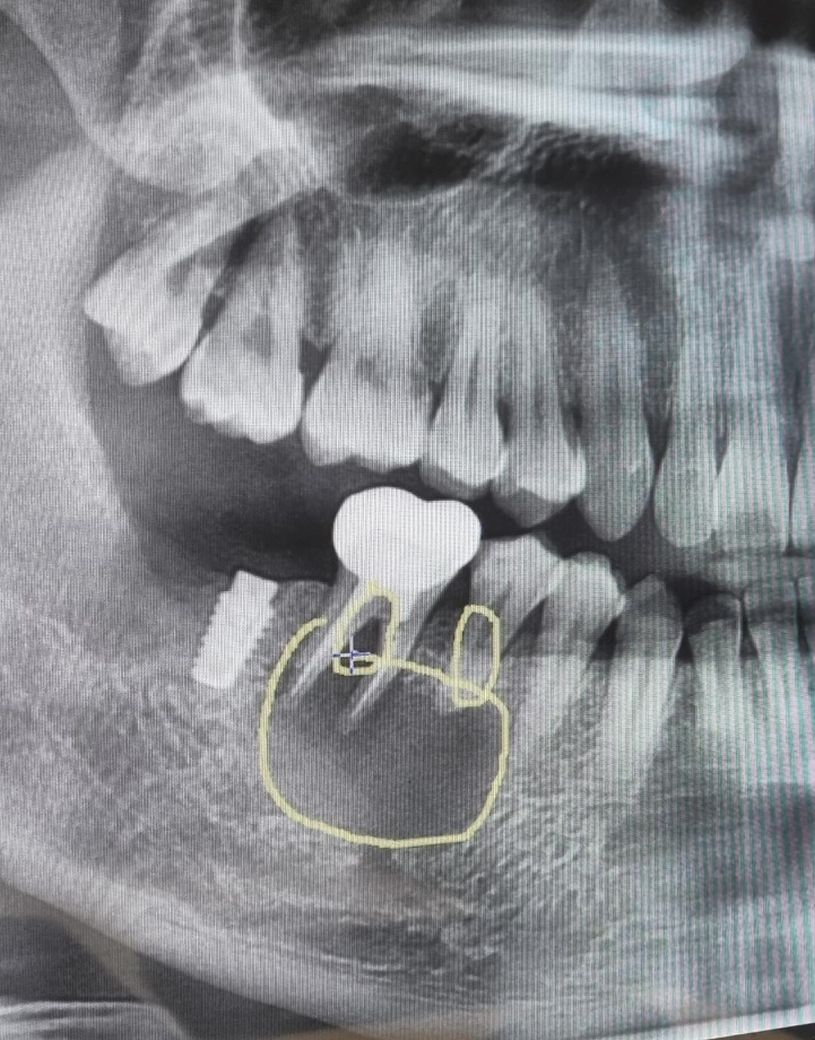

후에 혹시나 다른 치과에서도 검사를 받는게 좋겠다 싶어 xray 재촬영했더니 아래 사진을 보고 염증이 심해서 발치2개 및 염증제거 후 뼈이식 및 임플란트를 해야한다고 하더라구요.

• 1번 째 사진

엑스레이 상으로는 잇몸뼈가 많이 녹아 잇는 상태처럼 보입니다. CT 촬영을 해서 정확히 판단을 해봐야겟지만 발치를 해야될 가능성이 높아 보입니다.

치아 뿌리의 낭종이 매우 크게 만들어져 있습니다 발치후에 내부에 감염물질을 제거하는것이 좋을것으로 생각됩니다 병소가 치아 2개를 포함하고 있기 때문에 2개의 치아를 발치해야 할것으로 생각됩니다.

1. 업로드된 엑스레이 사진을 보면 임플란트 옆 두 개 치아의 잇몸뼈가 염증으로 많이 녹아있는 상태가 관찰됩니다

2. 진단은 맞는것 같습니다

3. 임플란트보다는 그 옆 치아들이 염증의 원인이지 싶습니다

4. 증상도 있으면 발치를 미룰 이유가 없습니다 저정도 염증은 치료 방법 없습니다